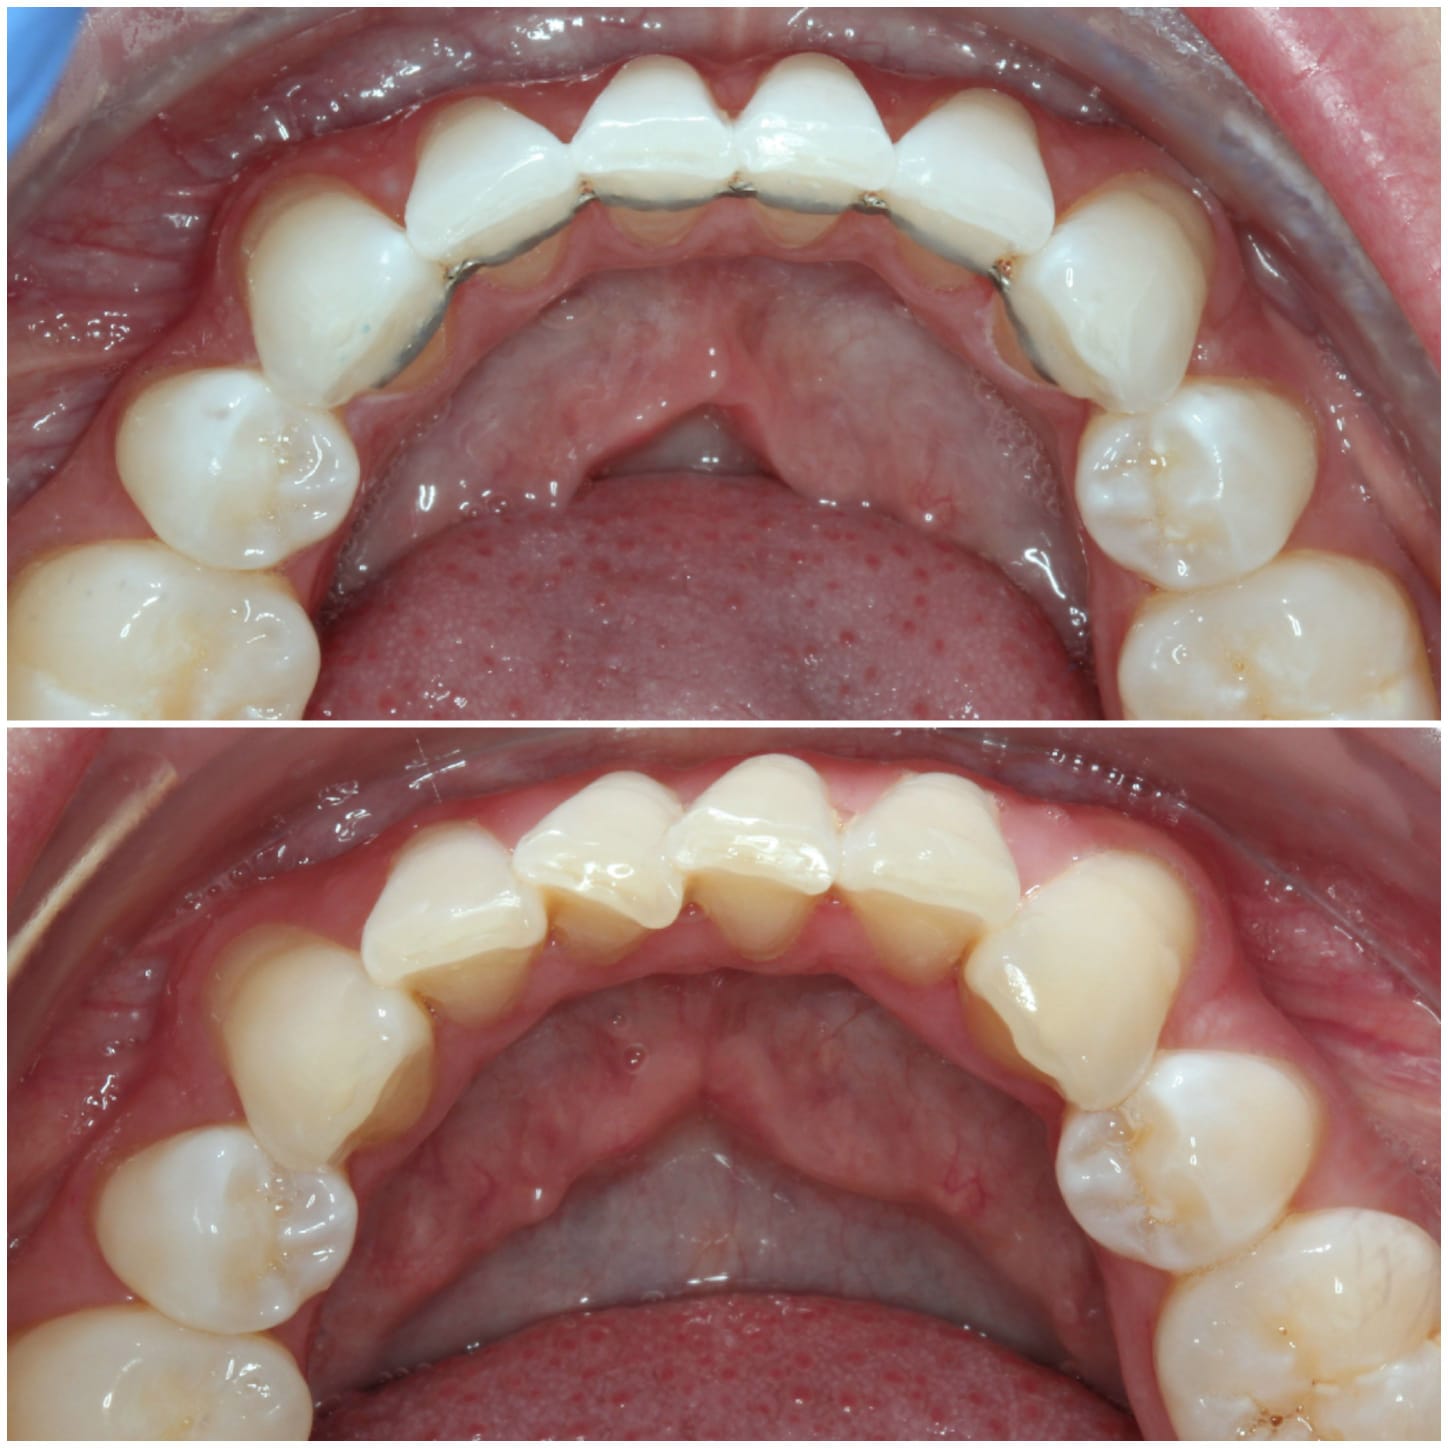

Invisalign is a well-known system for straightening teeth in the most discreet way. It works by using a series of clear aligners that fit comfortably over the teeth to gently move them into the desired position over time. There are no fixed brackets or wires used, in fact, the aligners are completely removable.

Virtually invisible way to straighten your teeth

Removable aligners make eating and dental care easy